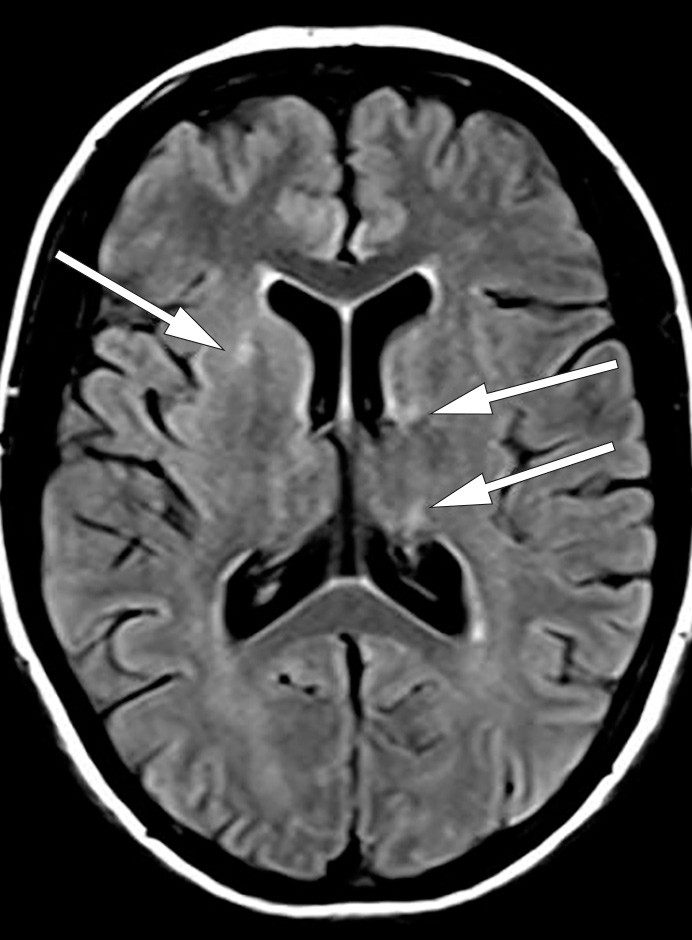

I løpet av et par dager ble pasienten somnolent og fikk økende muskeltonus i alle fire ekstremiteter, økte reflekser og bilateral plantarinversjon. CRP steg til 130 mg/l (< 5 mg/l), leukocytter til 18 · 10⁶/l (4,5 · 10⁶/l) og SR til over 100 mm/h. Gjentatte spinalpunksjoner viste lett leukocytose (16 · 10⁶/l celler) og lett forhøyet totalprotein (0,66 mg/l). Isoelektrisk fokusering av spinalvæske var uten tegn til intratekal IgG-produksjon. EEG endret seg på seks dager fra nærmest normalt til svært patologisk, med generalisert høyspent, langsom theta- og deltaaktivitet samt hyppige, skarpe potensialer frontotemporalt med trifasisk utseende. MR caput viste progresjon av signalavvikene i mediale venstre temporallapp (amygdala, uncus og fremre hippocampus) i basalgangliene og subkortikalt i begge hemisfærer (fig 2a og b).

Pasientens tilstand ble ytterligere forverret. Hun reagerte ikke på smertestimulus eller tilrop, ble spastisk i alle ekstremiteter, nakkestiv og hadde bilateral plantarinversjon. MR caput viste ytterligere progresjon av høysignalområder i begge hemisfærer, både i basalganglier, subkortikalt og kortikalt (fig 3). På grunn av manglende respons på steroider og immunoglobuliner samt rask og betydelig klinisk forverring, valgte vi å starte med immunsuppressiv behandling i form av rituximab 1 000 mg intravenøst.

Et par dager etter første infusjon var pasienten i klinisk bedring. Hun kunne kommunisere med korte setninger, ga blikkontakt og beveget armer og bein på oppfordring. Hennes kliniske tilstand ble imidlertid forverret rett før andre rituximabdose to uker senere. Pasienten ble sløv og trøtt, etter hvert ikke kontaktbar, hadde blikkdeviasjon mot venstre, bilateral plantarinversjon og feber. Undersøkelse av spinalvæske viste nå 409 · 10⁶/l celler (3/4 polynuklære) og totalprotein på 1,2 g/l. Nye MR-bilder av hjernen viste progresjon av forandringene i hvit substans, først og fremst i venstre hemisfære, men noe tilbakegang av signalforandringene subinsulært på venstre side.

Pasienten fikk andre rituximabdose og startet med prednisolon 30 mg daglig. En måned etter behandling kunne hun gå med støtte, hadde lett dysartri og apraksi. Hennes kliniske tilstand ble stadig bedre. MR caput utført to måneder etter andre rituximabinfusjon viste nærmest fullstendig tilbakegang av områdene med økt T2-signalintensitet i hvit substans rundt sideventrikler og i basalganglier.